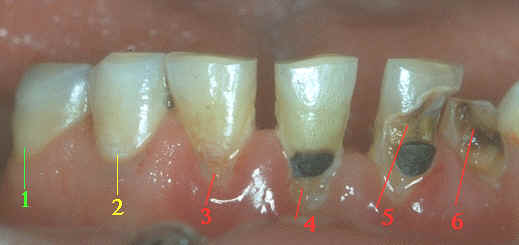

En la fotografía se observan las distintas etapas de dicha

desmineralización en superficies lisas: |

Photo and Pagemaker: D. Bratthall |

| 1-

Superficie dental sin caries. |

| 2-

Los primeros signos de desmineralización, es una mancha blanca.

No es aún una cavidad, la superficie es todavía uniforme. Con

medidas apropiadas, (las

aplicaciones de flúor realizadas por el

profesional y la indicación de usar una pasta con pH bajo y

alto contenido de flúor) el

proceso de caries puede ser parado aquí y hasta invertido. |

| 3-

La superficie de esmalte se ha estropeado. Ahora es una caries dental superficial de fácil

restauración por el profesional. |

| 4-

Una obturación o relleno ha sido hecho, pero como se

puede ver, el proceso de desmineralización a continuado y la lesión

de caries rodea el relleno. Esto se

llama Caries Secundaria; pero de hecho, esto es por lo general, la

misma enfermedad que está en progreso. |

| 5-

La desmineralización continúa y destruye la pieza dental

infectando al órgano pulpar más conocido como nervio. |

| 6-

Si el proceso continúa se produce la fractura de la pieza

dental. |